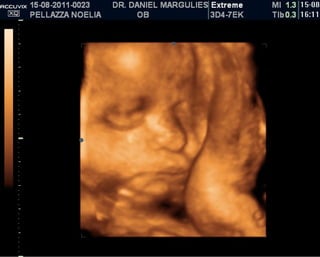

ISABELLA!

ISABELLA! Está viniendo!